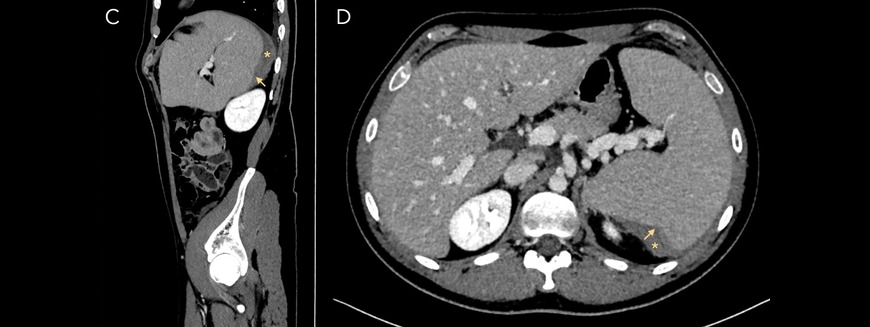

Diagnostic Oversights in Underrecognized Hemoglobin Variants

Hemoglobinopathies are among the most common inherited red blood cell disorders, yet they remain underrecognized in routine clinical practice.